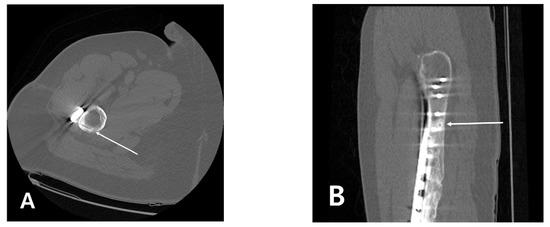

Subtrochanteric Insufficiency Fracture Occurring 5 Years after Surgery at the Steinmann Pin Insertion Site for Fracture Reduction